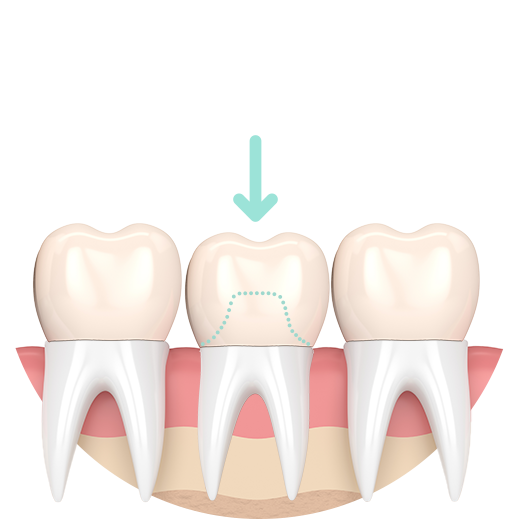

Preparation for a Crown

Damaged natural crown

Reshaped tooth

Porcelain crown